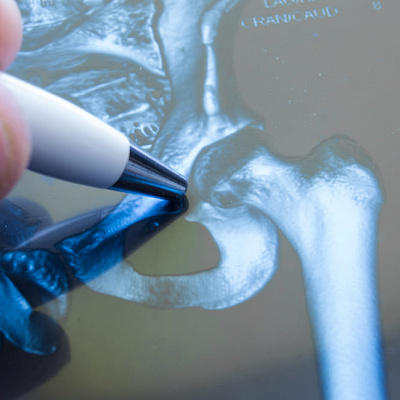

- рентген (проводится всегда, но на ранних стадиях часто не дает полного представления о характере патологического состояния);

- компьютерная томография, во много раз более точный метод лучевой диагностики, помогает определить заболевание даже на самой ранней стадии, когда симптомов расстройства еще нет;

- сцинтиграфия, определение характера изменений возможно по распределению радиоизотопного препарата, можно обнаружить патологический процесс еще на стадии нарушений кровотока, когда расстройство только-только развивается.